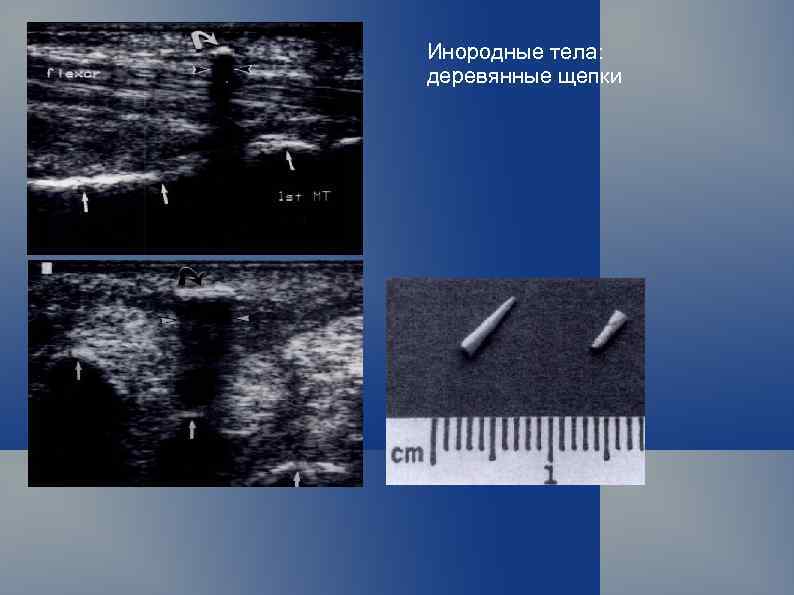

Инородные тела: деревянные щепки